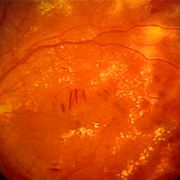

简介:糖尿病视网膜病变,糖尿病性视网膜病变(Diabetic Retinopathy,DR)常被称作糖尿病视网膜病变,指一系列由糖尿病导致视网膜微血管损害引起的病变,是常见的糖尿病慢性并发症之一,也是导致成人失明的主要原因之一。本病严重威胁糖尿病患者生存质量的同时,也给社会带来严重的经济负担。

- 糖尿病视网膜病变糖尿病视网膜病变是什么意思糖尿病性视网膜病变属于糖尿病的严重并发症的一种,是糖尿病性微血管病变中最重要的表现,是一种具有特异性改变的眼底病变,根据是否出现视网膜新生血管为标志,将没有视网膜新生血管形成的糖尿病性视网膜病变称为